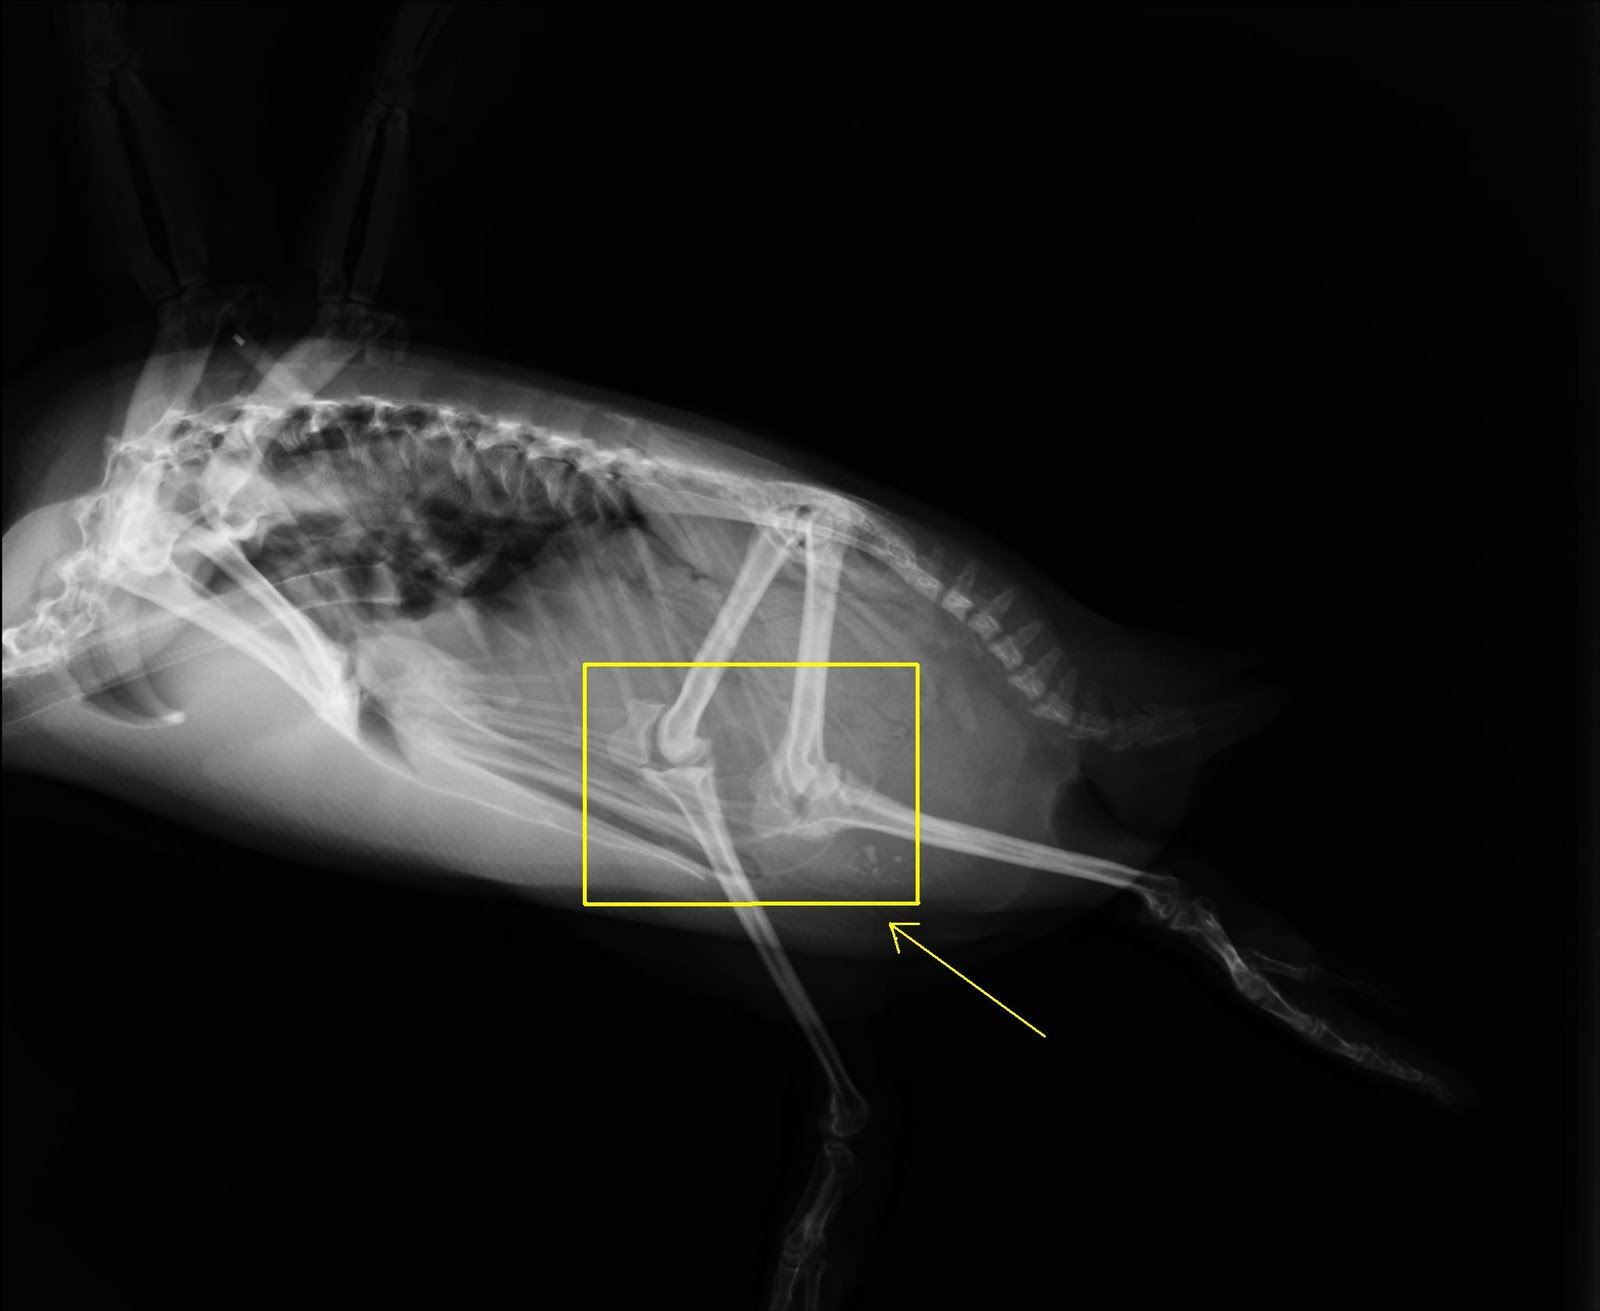

Timbul satu persoalan, adakah penguin mempunyai lutut sama seperti manusia?

Jawapannya, ya. Penguin juga mempunyai lutut sama seperi manusia, dan lututnya terletak dalam badan, disebalik bulunya yang tebal.